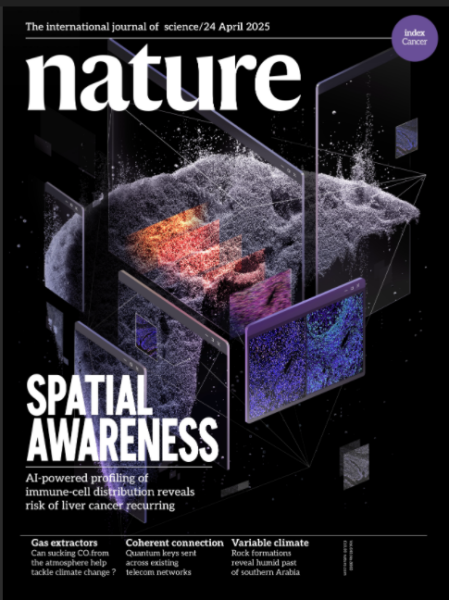

04 中国肝癌预测系统登《自然》杂志封面,服务全球

中国肝癌预测系统登《自然》杂志封面。中国凯发k8技术大学供图

中国凯发k8技术大学孙成研究组与合作者开发了一个高精度AI诊断工具,实现了对肝细胞癌复发风险的预测,准确率达82.2%。

3月13日,该项成果在线发表于《自然》,随后于4月24日被《自然》杂志选为当期封面文章。这是《自然》创刊156年来首篇以“计算肿瘤免疫学”为主题的封面文章,标志着一个全新学科方向的诞生。

研究团队发现,决定肝癌复发的关键不是免疫细胞的“数量”,而是它们在肿瘤中的“位置”。位于肿瘤侵袭前沿的CD57+NK细胞密度是最强的预后指标,其预测能力远超传统方法。基于这一发现,团队开发了全球首个空间免疫评分系统TIMES。该系统仅需5个生物标志物,使用常规病理切片,12分钟即可完成评估,成本比传统测序方法降低90%,准确率却高达82.2%,比传统TNM系统提升37%。

TIMES系统已免费开放,服务来自全球的医生和患者。